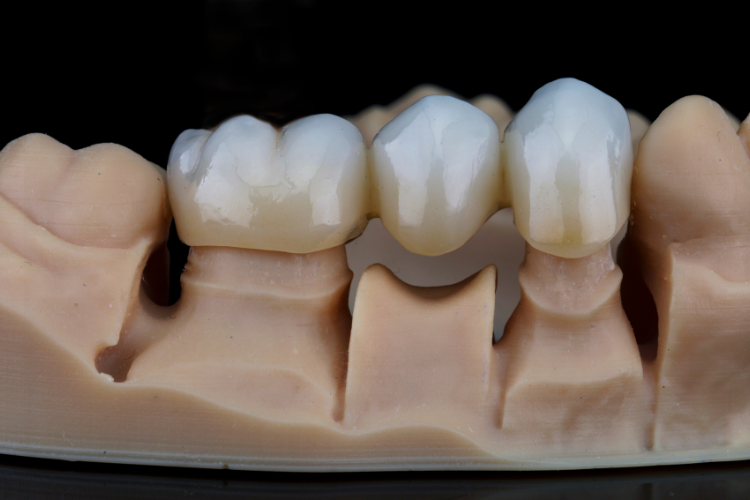

Impressions of the abutment and surrounding teeth are taken to create a custom crown that matches the size, shape, and color of the natural teeth. The crown is typically made of materials such as porcelain or ceramic.